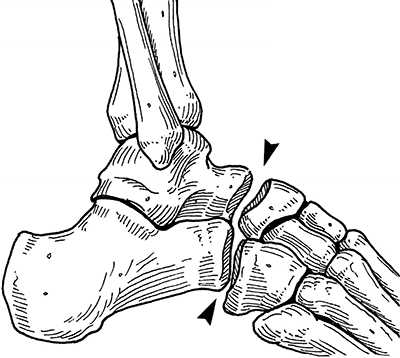

Строение сустава

Поперечный сустав предплюсны или сустав Шопара состоит из таранно-ладьевидного и пяточно-кубовидного суставов. В обоих суставах есть фасетки овальной формы, ось которых проходит по наибольшему диаметру овала. В нейтральном положении стопы оси находятся под углом, а в положении пронации стопы оси становятся параллельными. В положении супинации угол между фасетками достигает максимума. Он больше, чем угол в нейтральном положении и чем угол в положении пронации. Головка таранной кости имеет выпуклую поверхность, а головка ладьевидной кости, которая сочленяется с ней, имеет, соответственно, вогнутую поверхность. Площадь фасетки таранной кости больше, чем площадь фасетки ладьевидной кости. В сагиттальной плоскости сустав Шопара расположен на расстоянии 32-36% от крайней точки пяточного бугра.

Рис. 1. Сустав Шопара с наружной и внутренней поверхности

Рис. 2. Сустав Шопара по тыльной поверхности стопы. Сустав включает в себя пяточно-кубовидный и таранно-ладьевидный суставы